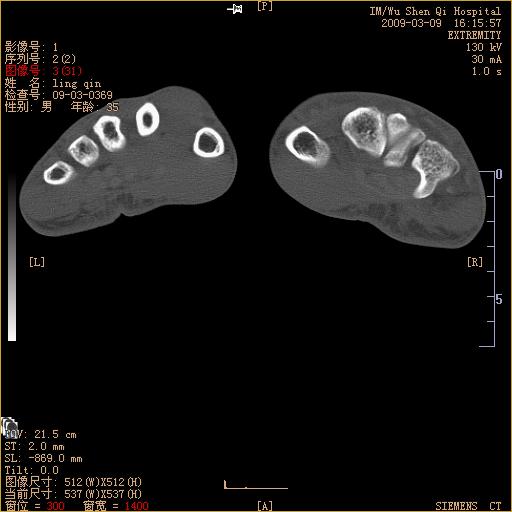

标题: CT18570:右手外伤10余天 [打印本页]

标题: CT18570:右手外伤10余天

请上传x线平片。舟状骨骨折可能大。

舟状骨骨折。

左侧舟骨及桡骨茎突骨折,第一掌骨基底部好像也有骨折,建议上传平片